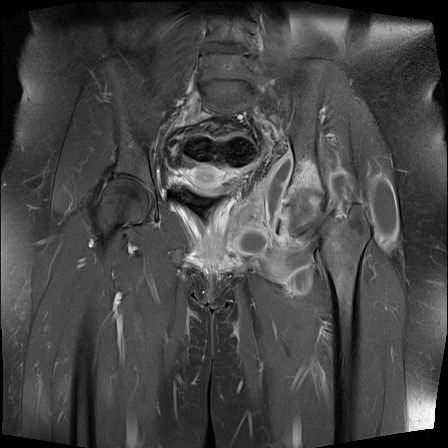

Hình ảnh X-quang khung chậu của bệnh nhân viêm khớp do lao tại khớp háng trái.

Có hẹp khe khớp kín đáo kèm theo xơ cứng dưới sụn tại khớp háng trái.

Các dấu hiệu X-quang này không đặc hiệu và rất có thể là biểu hiện của thoái hóa khớp.

Tiếp tục xem hình ảnh MRI…

Điều bất ngờ với tất cả mọi người là có nhiều ổ áp-xe.

Khi hình thành áp-xe lan rộng như vậy trong khi biểu hiện lâm sàng lại tối thiểu, cần luôn nghĩ đến viêm khớp do lao.

Chẩn đoán viêm khớp do lao được xác lập bằng chọc hút dịch khớp.